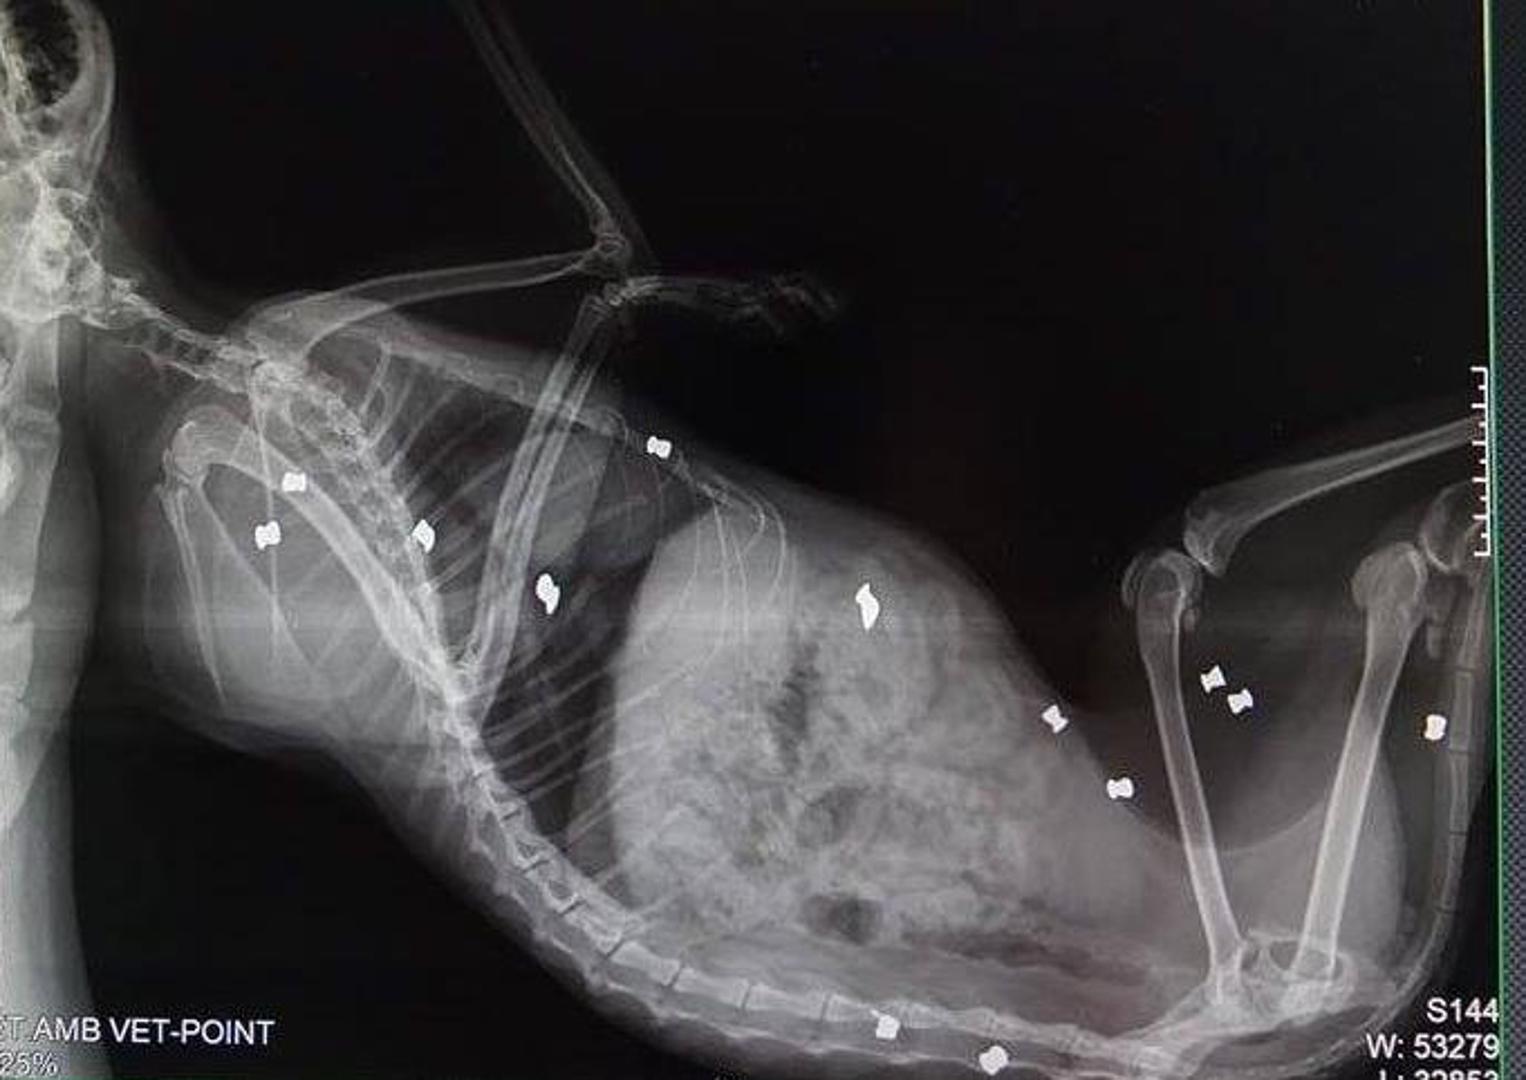

Maca Milica u tijelu je imala 13 metaka

– Mila je već bila kastrirana. Veterinar je htio provjeriti što je s nogicom, a rtg je pokazao da je puna metaka – objašnjava nam. Izbrojili su ih 13, neki su bili vrlo blizu kralježnice. Pet ih je odmah izvađeno, a što će biti s ostalima još nije odlučeno.